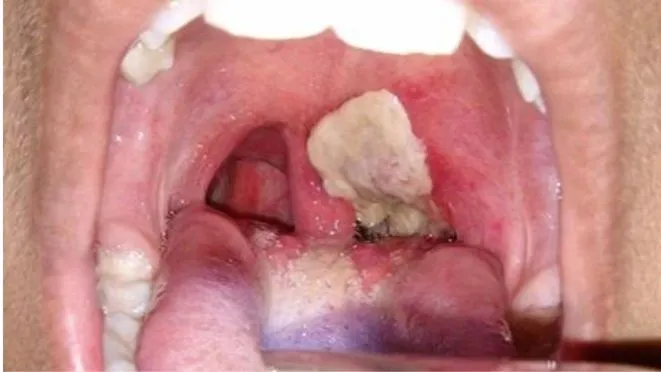

*Ngày 10-7, ngay sau khi có thông tin bệnh nhân P.H.D. (sinh năm 1968, ngụ huyện Hương Khê, tỉnh Hà Tĩnh) nghi mắc bệnh bạch hầu, Trung tâm Kiểm soát bệnh tật (CDC) Hà Tĩnh đã tiến hành điều tra dịch tễ bệnh nhân, lấy mẫu gửi Viện Vệ sinh dịch tễ Trung ương làm xét nghiệm (đang chờ trả lời kết quả). Đồng thời, phối hợp Trung tâm Y tế huyện Hương Khê khẩn cấp phun hóa chất tiêu độc khử trùng tại khu vực nhà bệnh nhân P.H.D. và điều tra lập danh sách khoảng 20 người tiếp xúc gần...

Hiện bệnh nhân đang điều trị tại Bệnh viện Bệnh nhiệt đới Trung ương để xét nghiệm khẳng định bệnh.